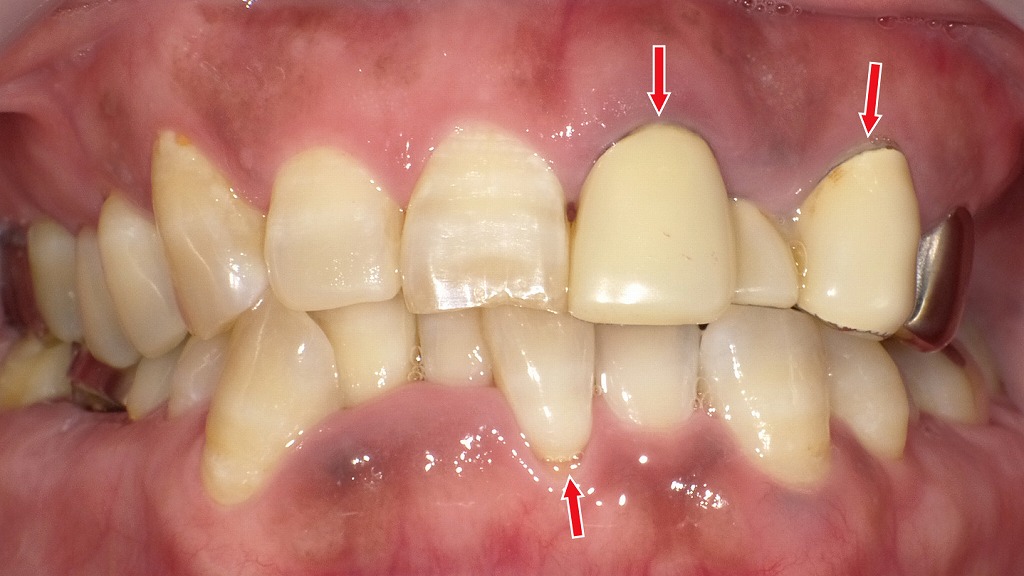

正しい歯磨きでここまで変わる:歯周病改善のビフォー&アフター

赤く腫れた歯ぐきと、クラウン周囲や前歯に付着したプラーク・歯石が見られ、歯周病が進行した状態です。

歯ぐきが腫れて盛り上がることで、歯と歯の境目が不明瞭になり、清掃が難しく悪循環に陥っていました。

丁寧なブラッシングとクリニックでのクリーニングにより、歯ぐきの腫れが軽減。

腫れが引いたことで歯ぐきが“下がったように見える”部分がありますが、これは歯周病が改善したサインです。

歯と歯ぐきの境目が明確になり、毎日の清掃がしやすい状態になりました。